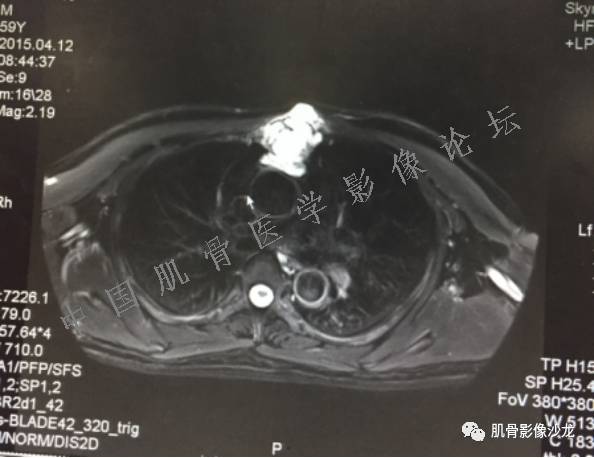

患者于2月前无明显诱因下出现腰骶部疼痛,夜间为重,逐渐加重伴左下肢麻木、疼痛,并有行走活动受限,在我院就诊,摄腰椎及骶髂部CT提示:腰椎骨质退变,腰3-4、4-5椎间盘膨出,骶髂关节炎。自用非甾体抗炎药无好转,再次来院就诊,门诊拟“骶髂关节炎”收住我科。病程无间歇性跛行,大小便正常。

专科检查:神清,脊柱无侧弯后凸畸形,椎体各节段无压、叩痛,双侧棘突旁无压痛,双侧骶髂关节压痛明显,左下肢放射痛,浅感觉较健侧减退,腰椎前屈后伸活动受限,膝、跟腱反射正常。

辅助检查:腰椎及骶髂部CT提示:腰椎骨质退变,腰3-4、4-5椎间盘膨出,骶髂关节炎。

雪舞 :第二例,位于骶骨,有骨质破坏并有软组织肿块,软组织肿块边界清

雪舞 :第二例挺难的,骨质破坏是溶骨性的,局部皮质中断,软组织肿块外缘光滑